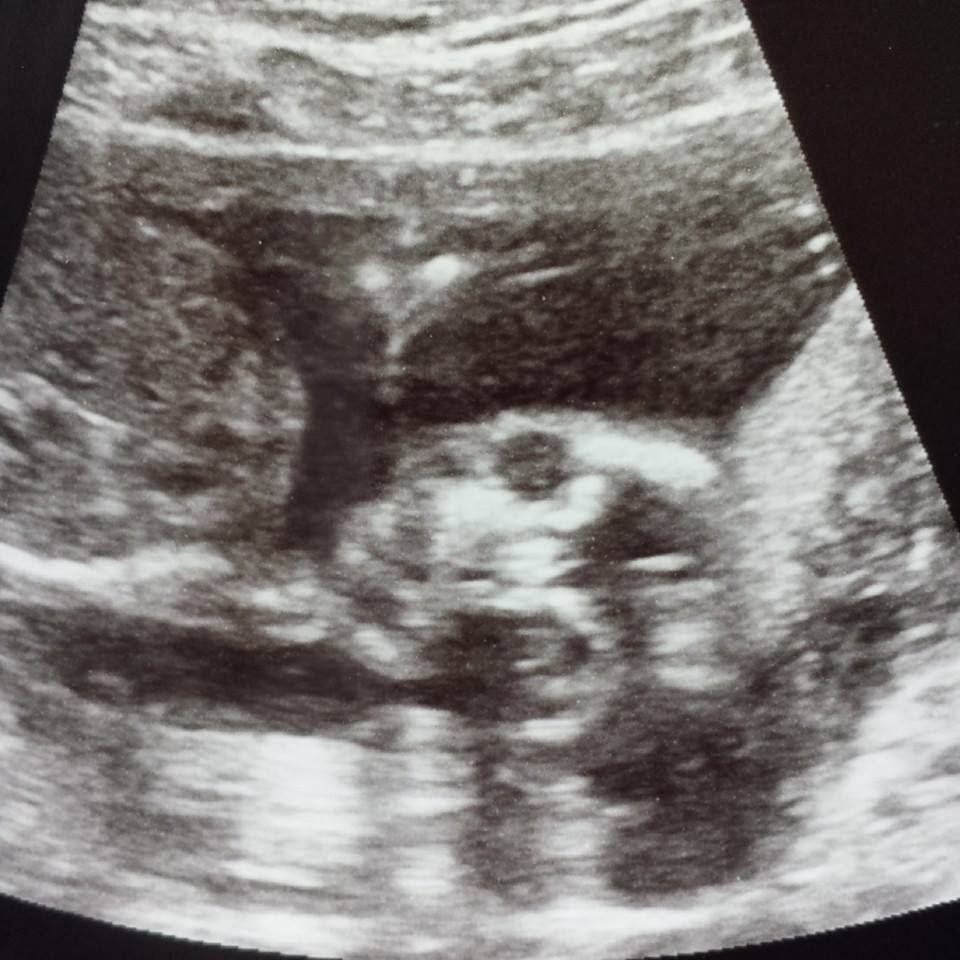

Catching Up (picture heavy post)

Week 19

So catching up....